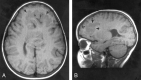

Background and purpose: Analysis of specific features in the brain of patients with holoprosencephaly (HPE) may clarify normal and abnormal brain development and help predict outcomes for specific children. We assessed sulcal and gyral patterns of cerebral cortex in patients with HPE and developed a method of grading brain development.

Methods: Neuroimaging studies (75 MR imaging, 21 CT) of 96 patients with HPE were retrospectively reviewed, with specific attention paid to the cerebral cortex. Thickness of cortex, width of gyri, and depth of sulci were assessed subjectively and by measurement. The angle between lines drawn tangential to the sylvian fissures ("sylvian angle") was measured in each patient with HPE and in 20 control patients.

Results: Thickness of cortex was normal in all 96 patients. Gyral shape and width and sulcal depth were normal in 80 patients. Twelve patients, all with very severe HPE and microcephaly, had reduced sulcal depth, diffusely in eight and limited to the anteromedial cortex in four with lobar HPE. Four patients had subcortical heterotopia, located anterior to the interhemispheric fissure, associated with shallow sulci in the overlying cortex. Sylvian fissures were displaced further anteriorly and medially as HPE became more severe, until, in the most severe cases, no sylvian fissures could be identified. Sylvian angle measurements corresponded closely with severity of HPE, being largest in the most severe and smallest in the least severe cases. All patients with HPE had sylvian angles significantly larger than the mean of 15 degrees measured in the control patients.

Conclusion: The only true malformations of cortical development were subcortical heterotopia. However, diffuse and focal abnormal sulci were observed. We propose our sylvian angle measurement of extent of frontal lobe development as an objective means of quantifying the severity of HPE.